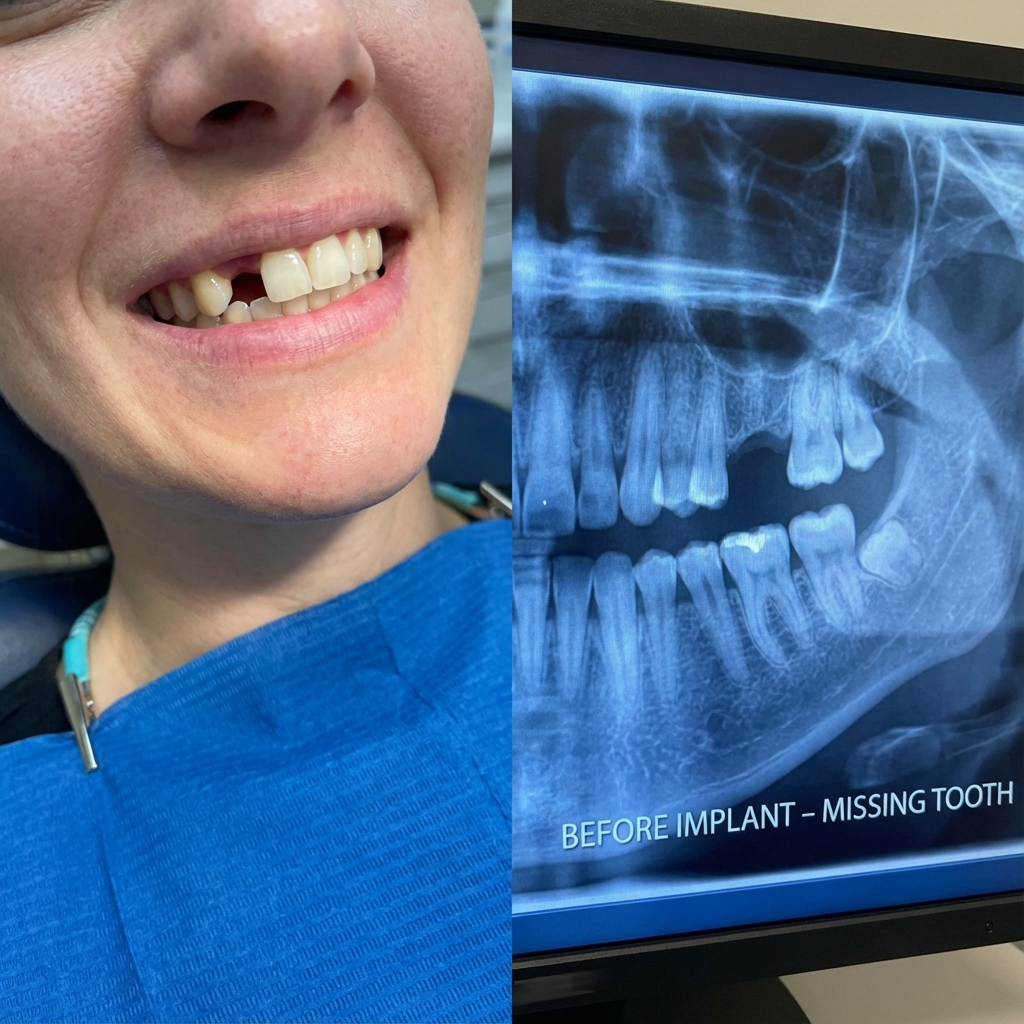

زراعة الأسنان

زراعة أسنان بأحدث التقنيات العالمية لاستعادة ابتسامتك الطبيعية

قبل وبعد

شاهد بعض نتائج عملائنا المذهلة

زراعة الأسنان

زراعة فورية